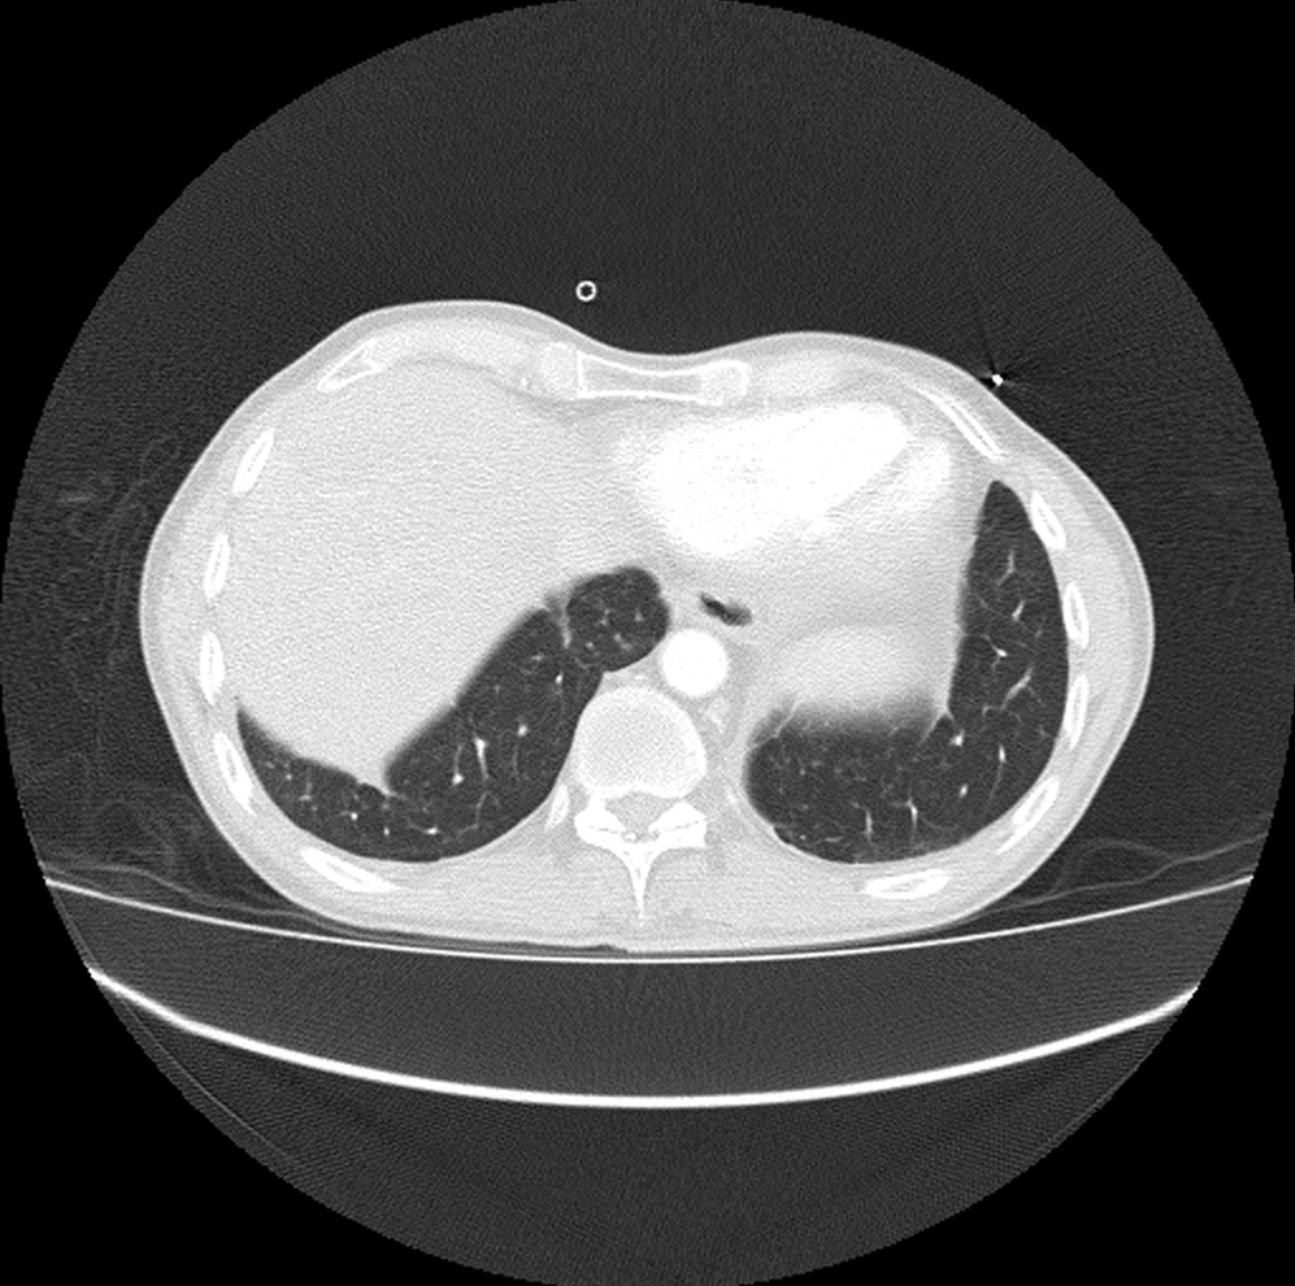

Hombre de 61 años asintomático. Colonoscopia demuestra válvula ileocecal ulcerada y estenótica. No hay antecedente de Enfermedad Inflamatoria Intestinal.

Con base en lo anterior el siguiente paso a seguir es?

a) Valoración por cirugía general.

b) Iniciar tratamiento con anti-inflamatorios e inmunosupresores.

c) Biopsia bajo guía ecográfica de las lesiones focales hepáticas.

d) Repetir colonoscopia.